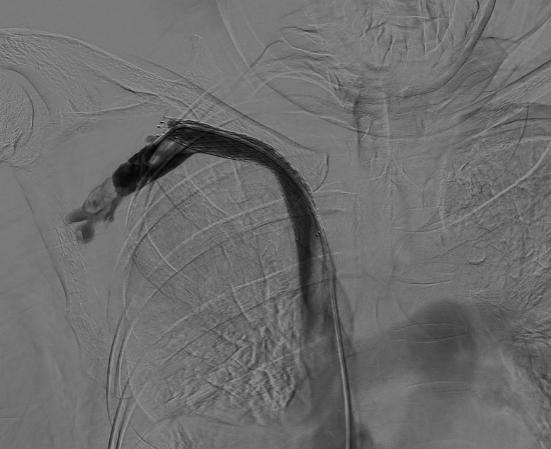

DSA引導(dǎo)下精準定位釋放支架成功,再次造影,頭臂靜脈閉塞段開通,血流可順利回流至上腔靜脈,但右側(cè)鎖骨下靜脈遠心端及腋靜脈可見血栓形成,遂予以留置導(dǎo)管溶栓治療。

術(shù)后3h,患者右上肢皮膚張力明顯緩解,術(shù)后24h,右上肢腫脹明顯緩解。

術(shù)后第2日,右側(cè)鎖骨下靜脈血栓范圍明顯縮小,右上肢腫脹完全緩解。